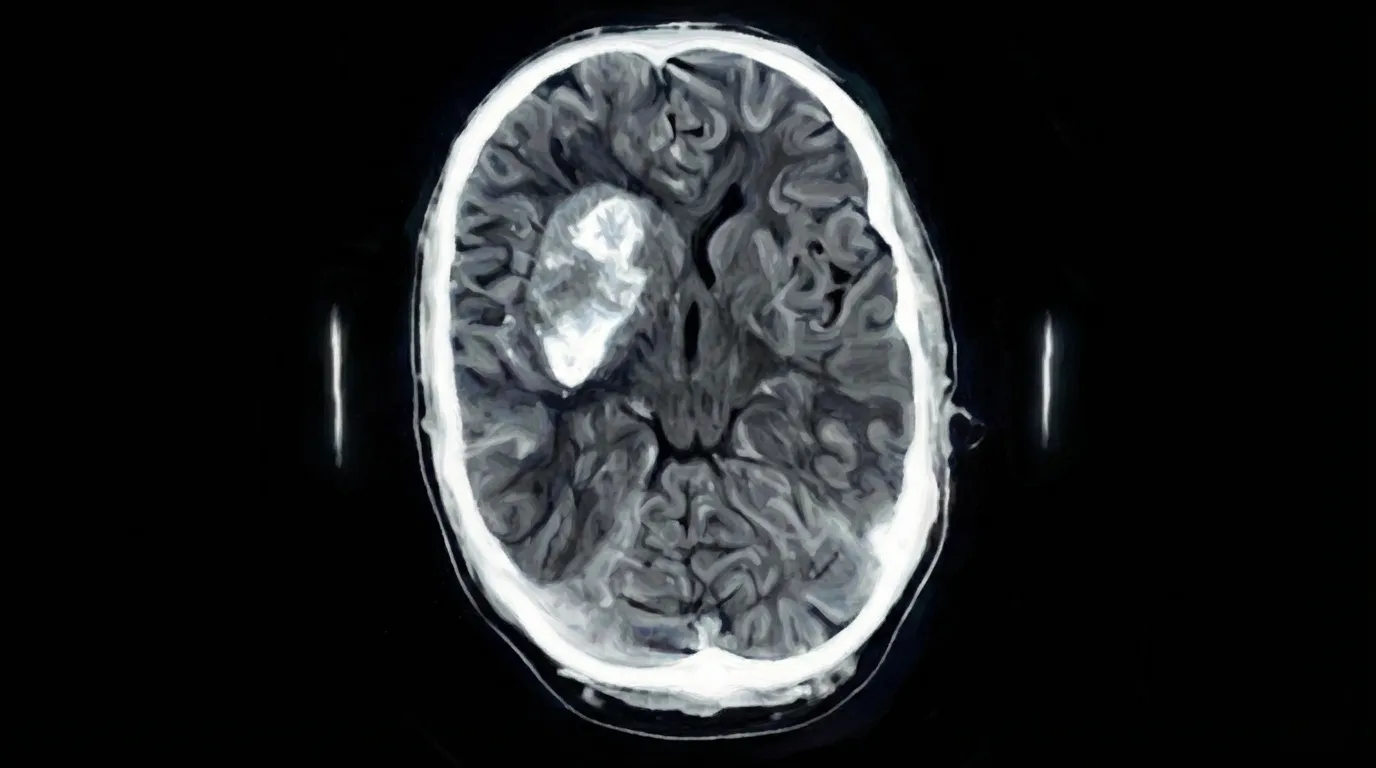

Craniotomia para Hematoma Intraparenquimatoso

Cirurgia para remover sangue que extravasou para dentro do tecido cerebral (parenquima), formando um coágulo que comprime e danifica as células nervosas ao redor.

1️⃣ Planejamento: Tomografia para localização precisa do hematoma.